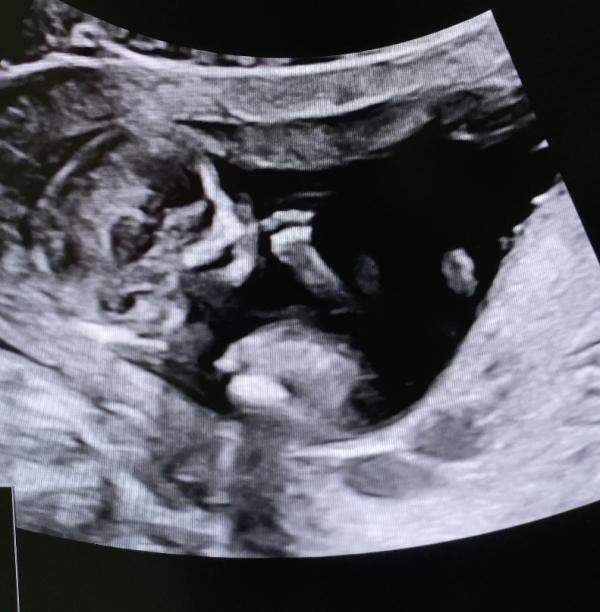

Первый скрининг 13н2д: Малыш кувыркается и сосет пальчик, все в порядке! Ура!

Сегодня был первый скрининг! Мой малыш уже полноценный человечек и самое главное с ним все в порядке! 😍 Кувыркается, сосет пальчик!

13н2д